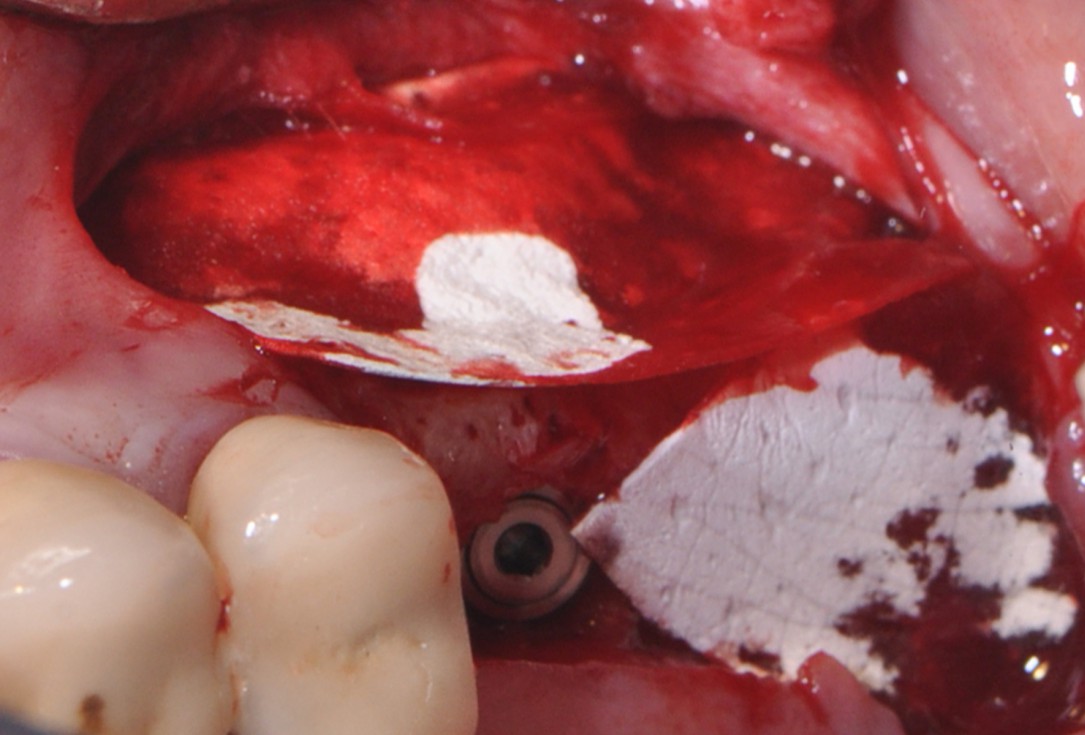

6/16 - collprotect® membrane protecting Schneiderian membrane

One-stage sinus lift - Dr. V. Kalenchuk

8/16 - Filling subantral cavity with cerabone® 1.0 -2.0 mm particle size

One-stage sinus lift - Dr. V. Kalenchuk

9/16 - Covering the augmentation site with collprotect® membrane

One-stage sinus lift - Dr. V. Kalenchuk